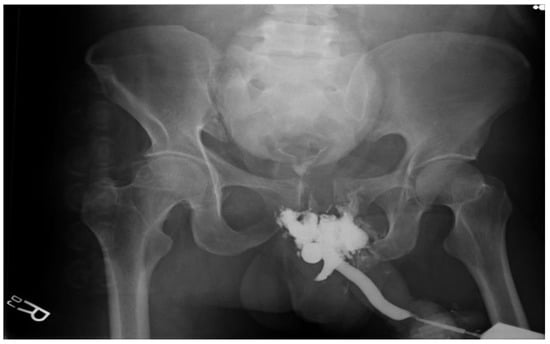

3.4. Blunt Urethral Injuries

3.4.3. Management

Posterior Urethral Injury